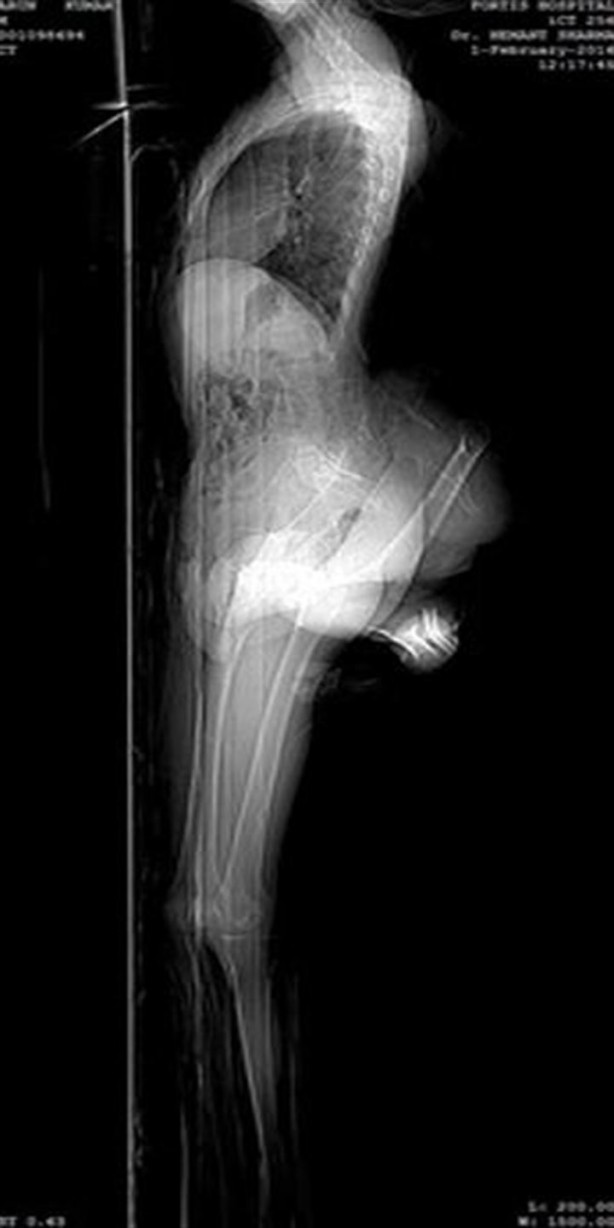

4 bacaklı adam görenleri hayrete düşürüyor

Hindistan'da 4 bacaklı olarak dünyaya gelen 20 yaşındaki Arun Rajput adlı genç bu rahatsızlığından dolayı yaşadığı köy halkı tarafından dışlandı.

Rajput, "İnsanlar bana gülüyor. Farklı göründüğüm için kimse bana saygı göstermiyor. Oysa ben onlardan biri gibi görünmek istiyorum. Ben de diğer insanlar gibi çalışmak istiyorum." dedi.

Ailenin dört çocuğunun en büyüğü olan Rajput'un en büyük hayali, fazladan olan uzuvlarından kurtulup öğretmen olmak.

Tarlalarda günlük yevmiyeye ırgatlık yapan fakir anne baba, oğullarını bazı doktorlara götürseler de duydukları tedavi ücreti karşısında boyun bükerek evlerine dönmüşler. 45 yaşındaki anne Lila Devi, "Oğlum evliliğimin 12. senesinde dünyaya geldi. Onun doğmasını sabırsızlıkla bekledik. Doğduğunda ise gözlerime inanamadım."

"Çok zayıftı, birçok doktora götürdük, hiçbiri garanti vermedi. İnsanlar ona kötü lakaplarla sesleniyorlar. O çok nazik bir çocuk. Sıkı çalışan ve saygı duyulacak bir hayat yaşamak isteyen bir genç adam. Umarım fazla bacaklarından kurtulur ve bizden biri olur." diyerek duygularını ifade etti.